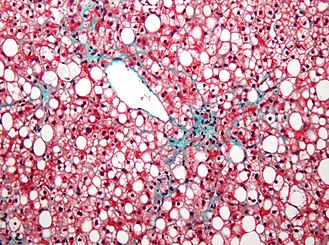

Steatosis. Elastic Masson's trichrome stain. | |

| LM | fatty change (macrovesicular or microvesicular and periportal or centrilobular), negative for ballooning degeneration, negative for significant inflammation - esp. neutrophils |

| Subtypes | macrovesicular steatosis (periportal, centrilobular), microvesicular steatosis |

Features - macrovesicular steatosis.

- One large vacuoles - similar to mature adipose tissue.

- Nucleus is eccentric.

Features - microvesicular steatosis.

- Multiple small (clear) cytoplasmic vacuoles - similar to brown fat, as seen in a hibernoma.

- Nucleus is central.[11]